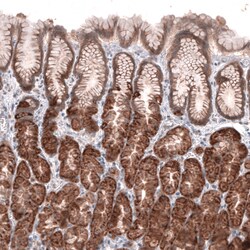

Invitrogen™ ACSL3 Polyclonal Antibody

Brand: Invitrogen™ PA582427

| Immunohistochemistry (Paraffin), Western Blot | |